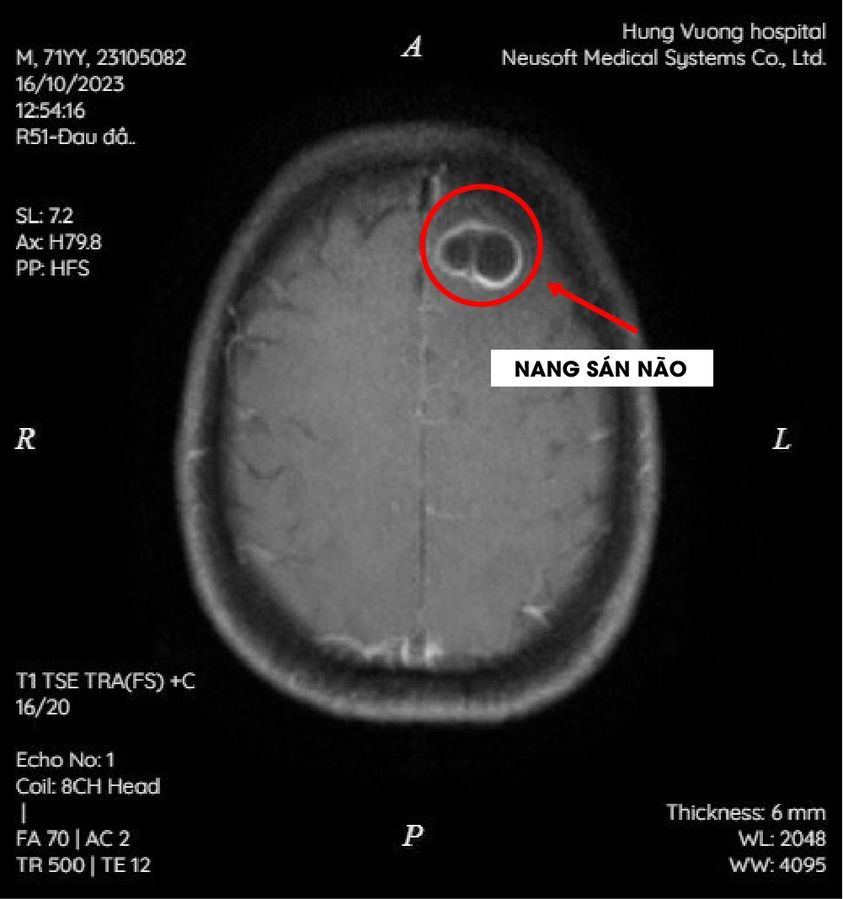

According to the results of blood tests and brain MRI, the doctor diagnosed that Ms. Duoc was infected with many worms in the brain, causing serious damage, bone marrow disorder, and low platelet count.

Therefore, it is necessary to prioritize treatment to stabilize platelets combined with doing the necessary tests to understand Ms. Duoc's current medical condition, then give an appropriate treatment regimen.